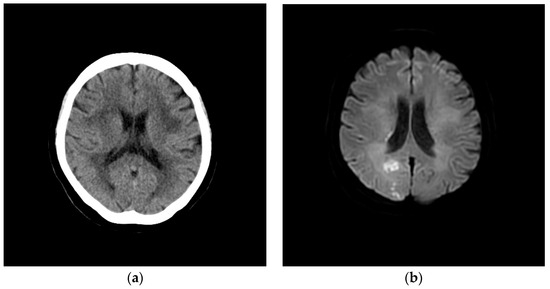

2. Case Presentation